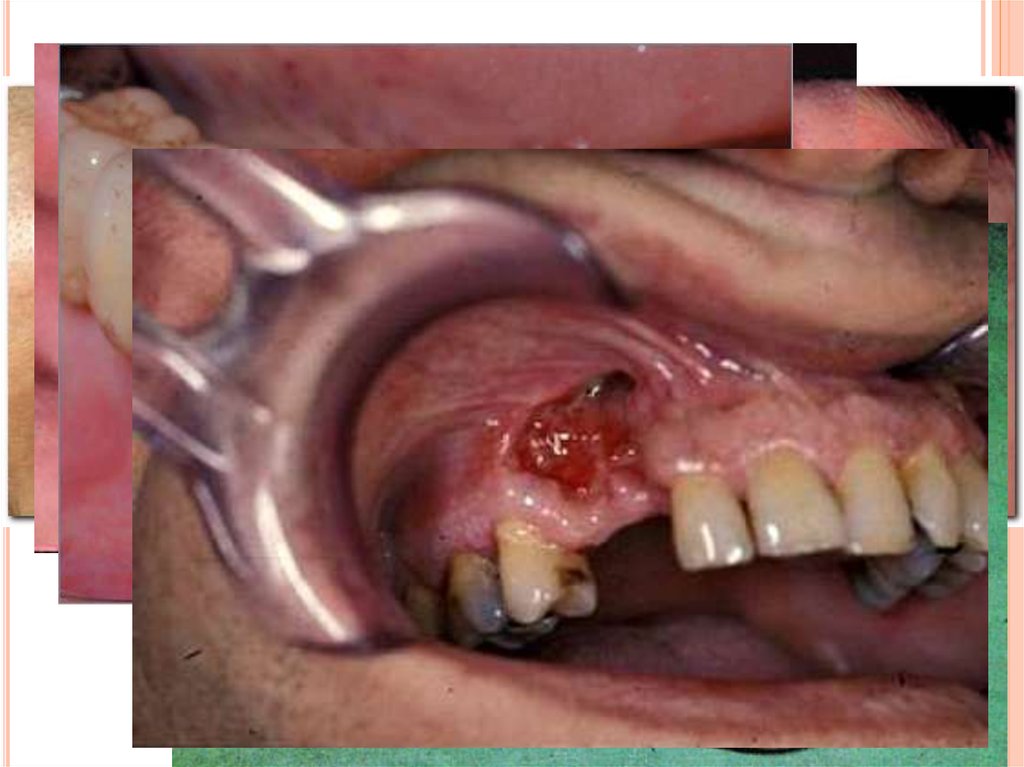

Воспалительный процесс из мягких тканей может

распространиться на надкостницу и кость. Примером тому

являются гнойный мастоидит, развивающийся при

воспалении среднего уха; костный панариций, являющийся

осложнением воспаления мягких тканей пальца;

остеомиелит нижней челюсти при кариесе зуба и пр.